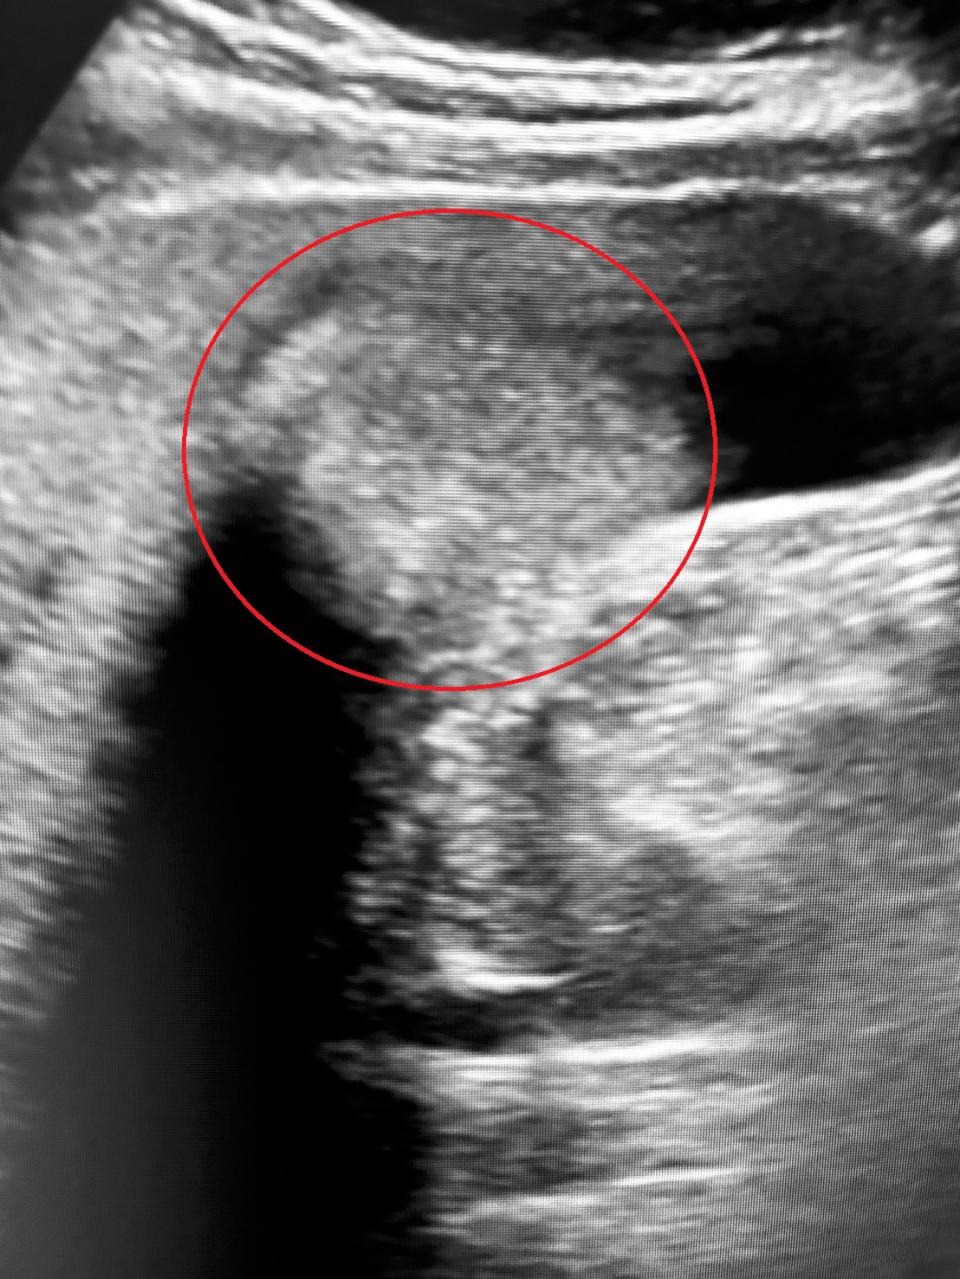

高市約70歲張姓老翁因胃痛、脹氣及右上腹劇痛就醫確診膽囊癌二期,博田國際醫院肝膽胰外科副院長李金德建議切除膽囊。李金德說,膽囊癌全球僅約0.5%,執刀近50年,經手膽結石癌變不足10例,根據外科教科書處理原則標準程序,切除張翁膽囊附著處肝臟與清除膽管旁淋巴,視癌細胞擴散情況安排化療或定期追蹤。膽結石如久未處理,可能衍生慢性膽囊炎、膽管結石、胰臟炎、膽管炎、黃疸甚至癌化風險,滿50歲膽結石病友每年約0.08%演變膽囊癌,建議如出現胃痛、右上腹不適等症狀速就醫檢查,掌握治癒先機。圖/博田國際醫院提供、文/高培德